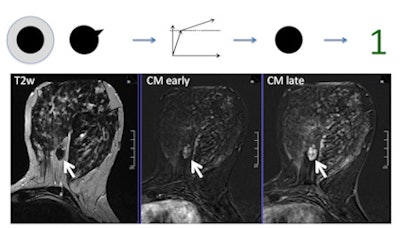

This shows a benign fibroadenoma. Following the Tree, it has no root sign, a persistent enhancement pattern (brighter in late as compared with early contrast enhanced image), and circumscribed borders, resulting in a node 1 (benign, minimum probability of cancer). No biopsy is necessary. In case the reporting radiologist would be unsure about the circumscribed margins, a node 3 (still benign) would result and still no biopsy should be performed.Interreader agreement was substantial to almost perfect (kappa: 0.643-0.896) for Tree and moderate (kappa: 0.455-0.657) for BI-RADS. Diagnostic performance using Tree was similar to BI-RADS. Less experienced radiologists achieved area under the curve (AUC) improvements up to 4.7% using Tree, while an expert's performance did not change (p = 0.526). The least experienced reader improved in specificity using Tree (16%, p = 0.001). The researchers found no further sensitivity and specificity differences.

This shows an invasive lobular cancer. The lesion presents with spiculations, corresponding to positive root sign. The brightness between early- and late-enhanced phases stays the same, corresponding to plateau enhancement. Finally, the T2-weighted scan shows no perifocal brightness, edema is negative. The resulting node is 7, biopsy is recommended. In case someone would rather see a persistent enhancement, node 6 (still biopsy recommended) would be the result."These results have important clinical implications: In addition to BI RADS, Tree provides specific guidance about what certain combinations of lesion features indicate with regard to potential malignancy," they wrote. "This simplifies and structures the process of lesion interpretation."